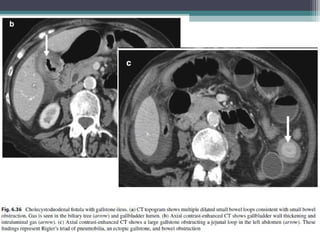

GALL STONE ILEUS

• Its associated with Cholecytsoduodenal fistula

• The gall stone passes into the duodenum by eroding the inflamed gall bladder

wall and leads to small bowel obstruction

• Clinical symptoms : RIGLERS TRIAD

 Pneumobilia

 Small bowel obstruction

 Ectopic gall stone usually in right iliac fossa

 Gas in biliary tree can be recognised by its branching pattern with gas being

more prominent centrally

 Gas in portal vein tends to be peripherally located in small veins around the

edge of the liver

 BOUVERET SYNDROME : Gastric outlet obstruction due to gall stones impacted

in the distal stomach or proximal duodenum